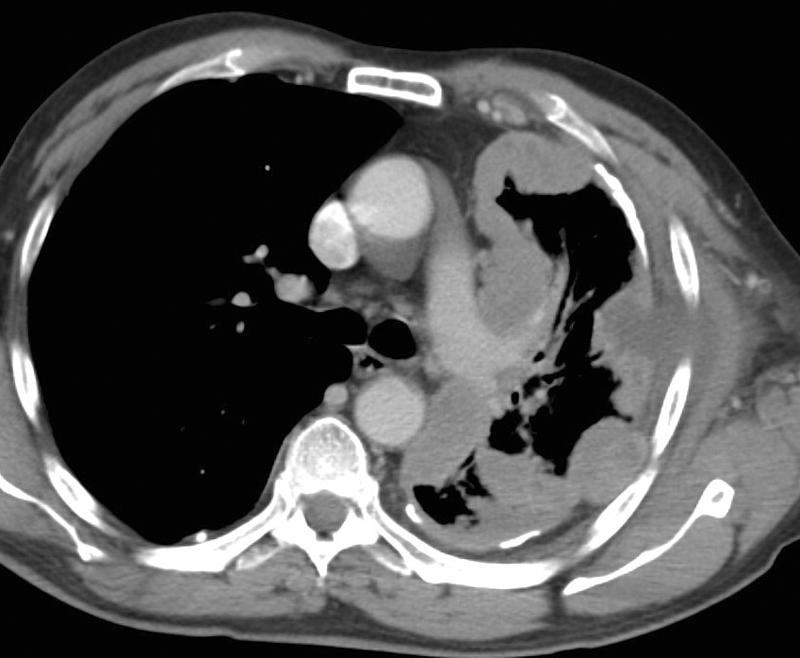

Gallery Pleural mesothelioma 3B + plaques CT

mesothelioma 3B

+ plaques CT